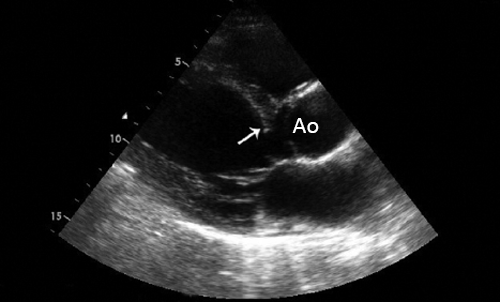

- ЭхоКГ. ЭХОКГ позволяет определить: структуру клапана (двустворчатый клапан, утолщение створок, фиброз, кальциноз, вегетации), характер его движения (подвижность створок, степень открытия) и площадь отверстия; изменения корня аорты (постстенотическая дилатация), объем левого желудочка, выраженность гипертрофии левого желудочка, нарушения локальной сократимости левого желудочка (указывающие на ИБС), ФВ, объем левого предсердия, состояние других клапанов. Доплеровское исследование позволяет с высокой точностью определить градиент давления между аортой и левым желудочком.

• Двустворчатый аортальный клапан (стеноз, регургитация).

Аортальный стеноз

• Площадь отверстия • Пиковая скорость >4.0 м/с.

• Средний градиент давления >40 мм рт. ст.